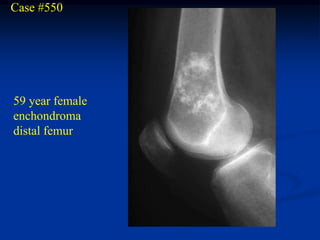

Case #550

59 year female

enchondroma

distal femur